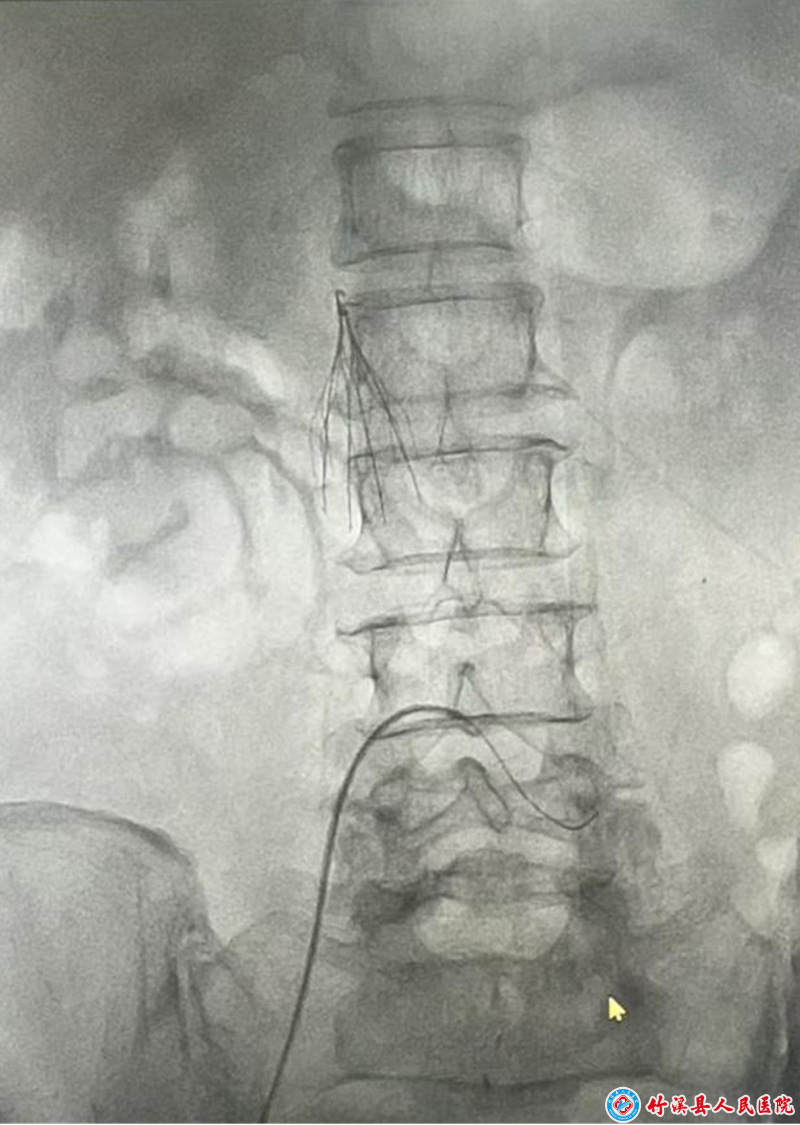

竹溪縣人民醫(yī)院訊(通訊員甘戈)2025910日,一場驚心動魄的生命救援在我院介入中心與腫瘤科上演。一名72歲高齡女性患者因突發(fā)廣泛深靜脈血栓合并急性肺栓塞命懸一線,在介入中心與太和醫(yī)院教授張曉龍的共同努力下,通過緊急實(shí)施廣泛深靜脈血栓下腔靜脈濾器植入以及經(jīng)導(dǎo)管溶栓術(shù),最終挽救了患者生命。

患者因突發(fā)左下肢腫脹疼痛被緊急送醫(yī)。檢查結(jié)果顯示:左下肢深靜脈全程血栓形成,同時合并右肺下葉肺動脈栓塞。介入中心用"雙重重?fù)?/span>"來形容病情的危急性:"深靜脈血栓如同定時炸彈,而肺栓塞則是已經(jīng)引爆的炸彈,患者隨時可能因呼吸循環(huán)衰竭死亡。"

時間就是生命!醫(yī)院立即啟動應(yīng)急救治流程。在張曉龍教授的指導(dǎo)下,醫(yī)療團(tuán)隊(duì)爭分奪秒制定手術(shù)方案。首先實(shí)施下腔靜脈濾器植入術(shù),為患者搭建"生命防護(hù)網(wǎng)",防止血栓再次脫落;隨后立即進(jìn)行導(dǎo)管接觸性溶栓術(shù),將溶栓導(dǎo)管精準(zhǔn)置入血栓部位,直接給藥溶解血栓。